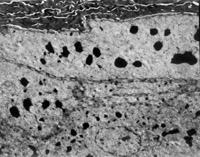

É˺ó12h¼±ÕïÈëÔº£¬ £¬ £¬£¬£¬£¬£¬¼ì²éË«ÏÂ֫Ϊdz¢ó¶ÈÉÕÉË¡£¡£¡£¡£¡£ ¡£¡£ ¡£´´Ãæ±íƤÒÑ»µËÀ°þÍÑ£¬ £¬ £¬£¬£¬£¬£¬ÕæÆ¤²ã±äÐÔ»µËÀ³ÊÀ¯»ÆÉ«ºÍÀ¯°×É«Ïà¼ä£¨Í¼5-3-1£©¡£¡£¡£¡£¡£ ¡£¡£ ¡£È¡¾Ö²¿×éÖ¯×ö²¡ÀíÇÐÆ¬¼ì²é£¬ £¬ £¬£¬£¬£¬£¬ÏÔʾÉÏÆ¤×é֯ȫ²ã»µËÀ£¬ £¬ £¬£¬£¬£¬£¬ÕæÆ¤²ã½ºÔ­ÏËά±äÐÔ£¬ £¬ £¬£¬£¬£¬£¬½á¹¹ÔÓÂÒ£¬ £¬ £¬£¬£¬£¬£¬Î¢Ñ­»·ðöÖÍ£¨Í¼5-3-2£©¡£¡£¡£¡£¡£ ¡£¡£ ¡£

5-3-2 ÉÏÆ¤×é֯ȫ²ã»µËÀ£¬ £¬ £¬£¬£¬£¬£¬½ºÔ­ÏËά±äÐÔ£¬ £¬ £¬£¬£¬£¬£¬Î¢Ñ­»·ðöÖÍ HE¡Á20